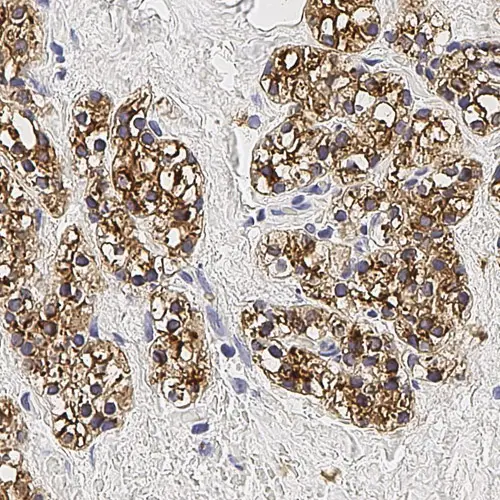

Human skin: immunohistochemical staining of LP34 (cytokeratins 5/6/18) localized throughout the epidermis, with the strongest staining in the stratum spinosum. There is an absence of staining in the dermis. Cytokeratin (5/6/18): clone LP34

Cytokeratins 5, 6 and 18 are reported to be expressed in a broad range of human epithelial tissues, from simple glandular epithelia to stratified squamous epithelia. These include epithelial cells that are ectodermal, mesodermal, or endodermal in origin. These cytokeratins have been reported to be expressed in tumor cells of epithelial origin and less commonly of mesothelial origin. Non-epithelial tumors such as lymphomas do not express these cytokeratins.

The recognition of cytokeratin 18 on formalin fixed paraffin embedded sections using clone LP34 may be variable.